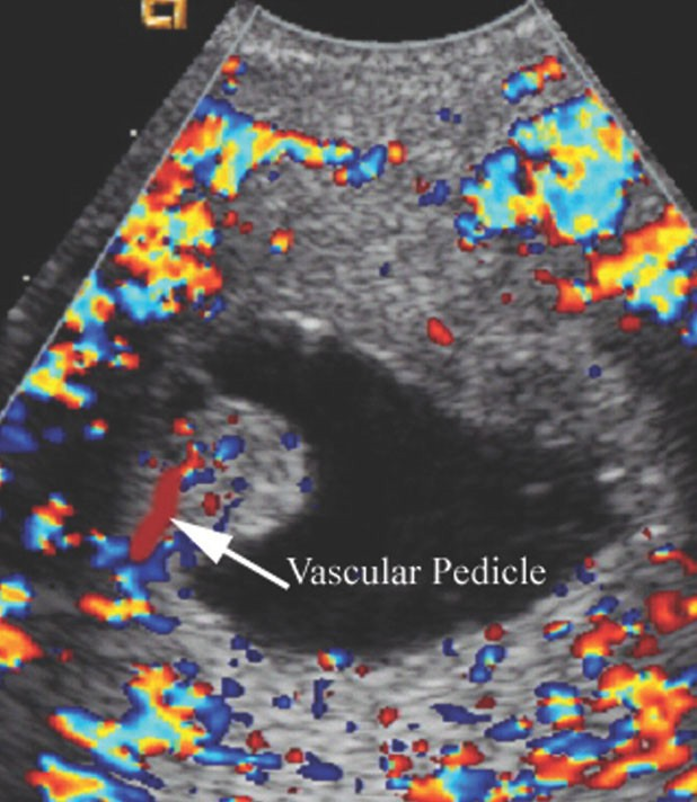

Uterine Polyp

*

(on a stalk)